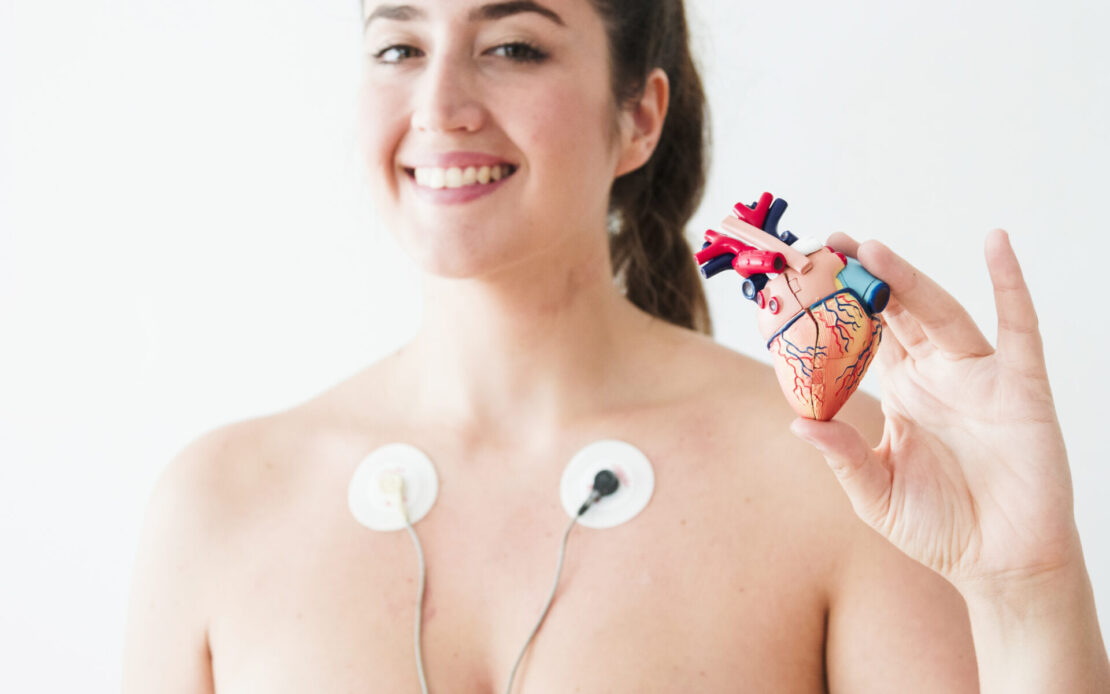

Diagnostica

Servizi diagnostici

Presso il Centro Medico, ci impegniamo a offrire una vasta gamma di servizi diagnostici specialistici di alta qualità, supportati da tecnologie avanzate e da un team di professionisti altamente qualificati. La nostra struttura è dotata di apparecchiature diagnostiche moderne, che garantiscono una diagnosi accurata per un trattamento mirato a tutela della tua salute.

- Cardiologia